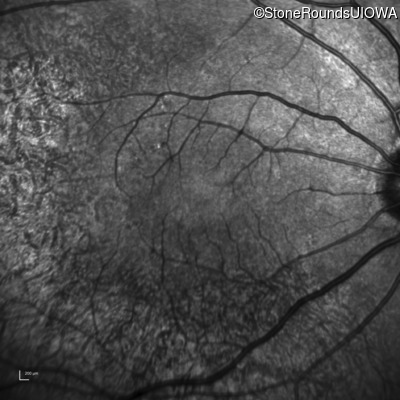

Infrared Fundus Photograph - Left - 20/20 -1

Exemplar